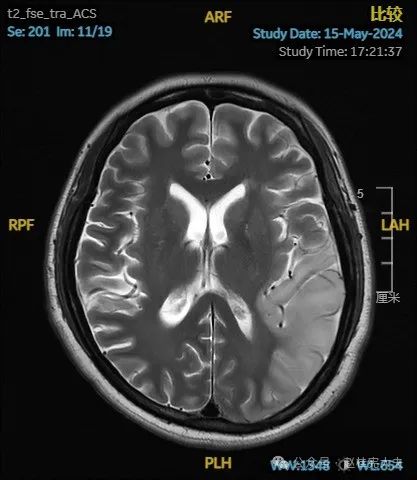

入院后给予精氨酸,左卡尼丁,辅酶Q10,维生素E等治疗。患者病情稳定好转中,2天后意识清楚,语言表达仍欠佳。当天复查颅脑磁共振如下:

以上为患者发病后3次的颅脑磁共振片子,临床诊断基本上可以确认了,希望患者逐渐恢复!